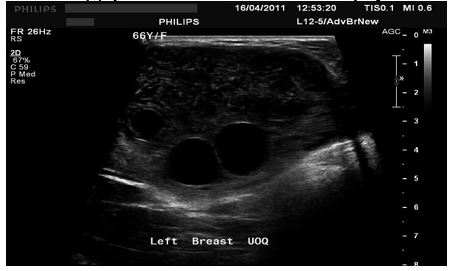

She had ultrasound scan of the breast which showed a large heterogeneous and lobulated mass within the upper quadrant of her left breast which had corresponded to the mammographic features. Few internal anechoic cysts were visualized within the peripheral aspects of the breast lesion. Doppler interrogated images did not show any internal vascularity within the mass (see figures 13, 14, and 15). There were no enlarged associated axillary lymph nodes found. She had ultrasound scan-guided biopsy from the lesion. She did have computed tomography (CT) scan for further assessment of the breast lump which did reveal a large hypo-dense mass within her left breast. It also revealed very tiny and thin internal septations were visualized. There was no peripheral enhancement and no internal enhancement. The mass did measure 6.8 cm x 6.2 cm x 9 cm in maximum dimensions (see figures 16 and 17). No axillary lymph nodes were found. The rest of the intra-thoracic and abdominal structures were found to be normal. Pathology examination of the biopsy specimen showed scanty material which had consisted of fragmented eosinophilic membranes that had laminated appearance in keeping with the diagnosis of hydatid cyst. A final diagnosis of hydatid cyst of the breast was made. The patient was referred to the surgeons for surgical excision of the hydatid cyst of the breast at the time of the report of the article. The lesson that needs to be learnt from this case report is the fact that diagnosis of hydatid cyst can be established pre-operatively with careful history taking, clinical examination radiology imaging including ultrasound scan, CT scan, and ultrasound scan-guided biopsy for histopathology/cytology examination which would guide the surgeon to undertake a careful complete surgical excision of the without spillage of the contents of the hydatid cyst.